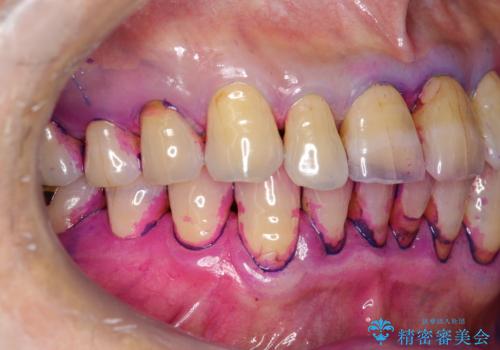

歯周病の治療前にまずはモチベーションUPにPMTCでステインの除去

担当医 歯科衛生士